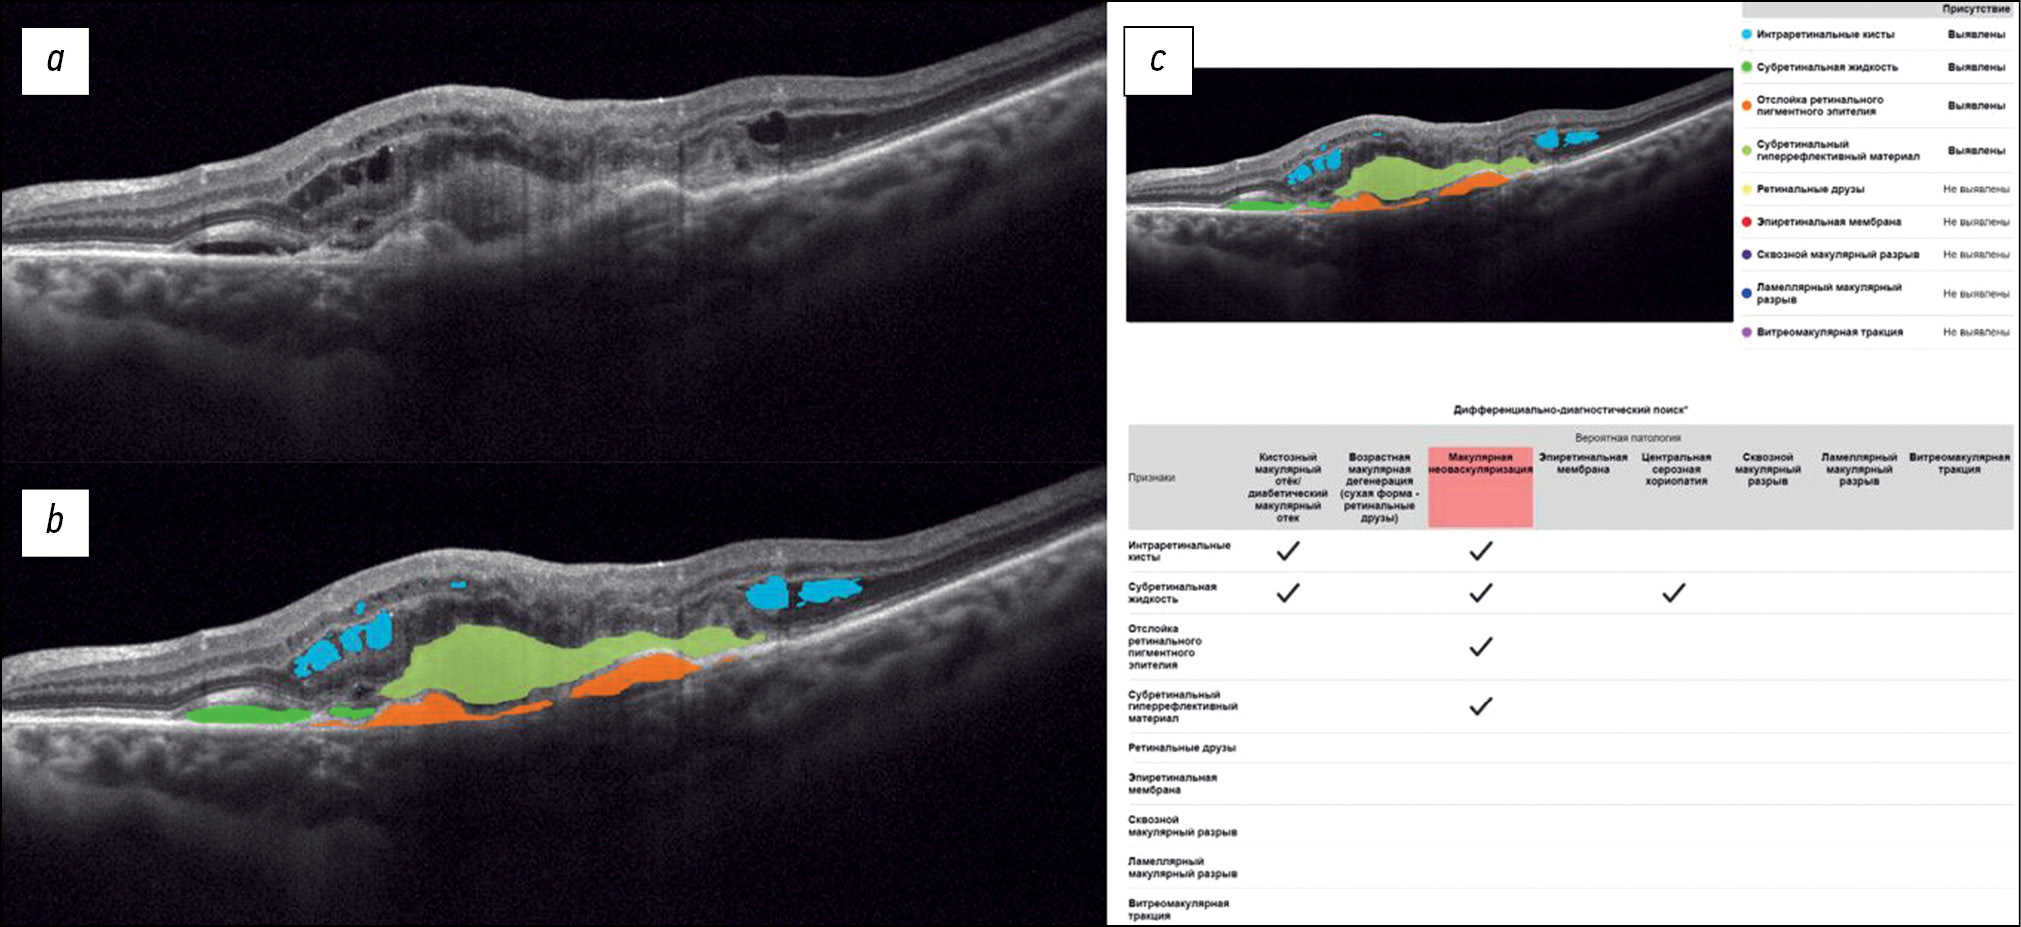

Fig. 1 shows a structural OCT scan of the macular zone of patient B (54 years old) with type 2 diabetes mellitus. The ophthalmologist’s report recorded DME. In the analysis of the structural OCT scan by Retina.AI, the algorithms segmented the following pathological signs: intraretinal cysts, subretinal fluid. In conclusion, the patient was diagnosed with DME.

Fig. 1. An example of the optical coherence tomography scan analysis of a patient with diabetic macular edema by the artificial intelligence algorithm: a — structural optical coherence tomography scan; b — optical coherence tomography scan after segmentation of the pathological features (subretinal fluid — green mask, intraretinal cysts — blue masks); c — scan analysis report (the reporting table of the differential diagnostic search, probable pathology is highlighted in red — macular edema).